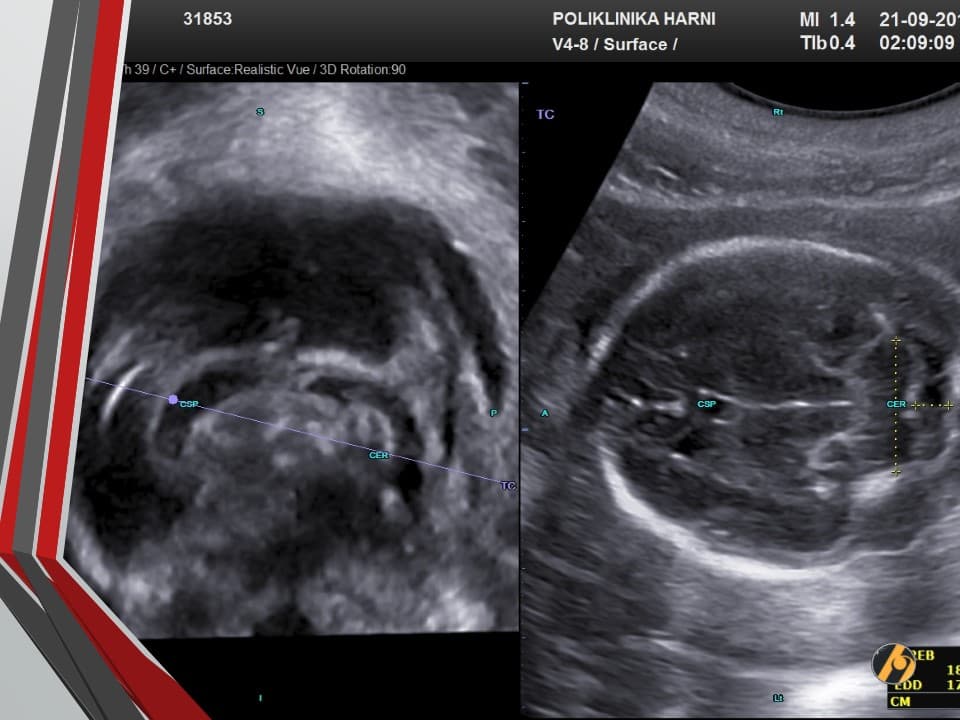

Vaša beba dugačka je oko 39 cm i teška 1,100 – 1,400 g.